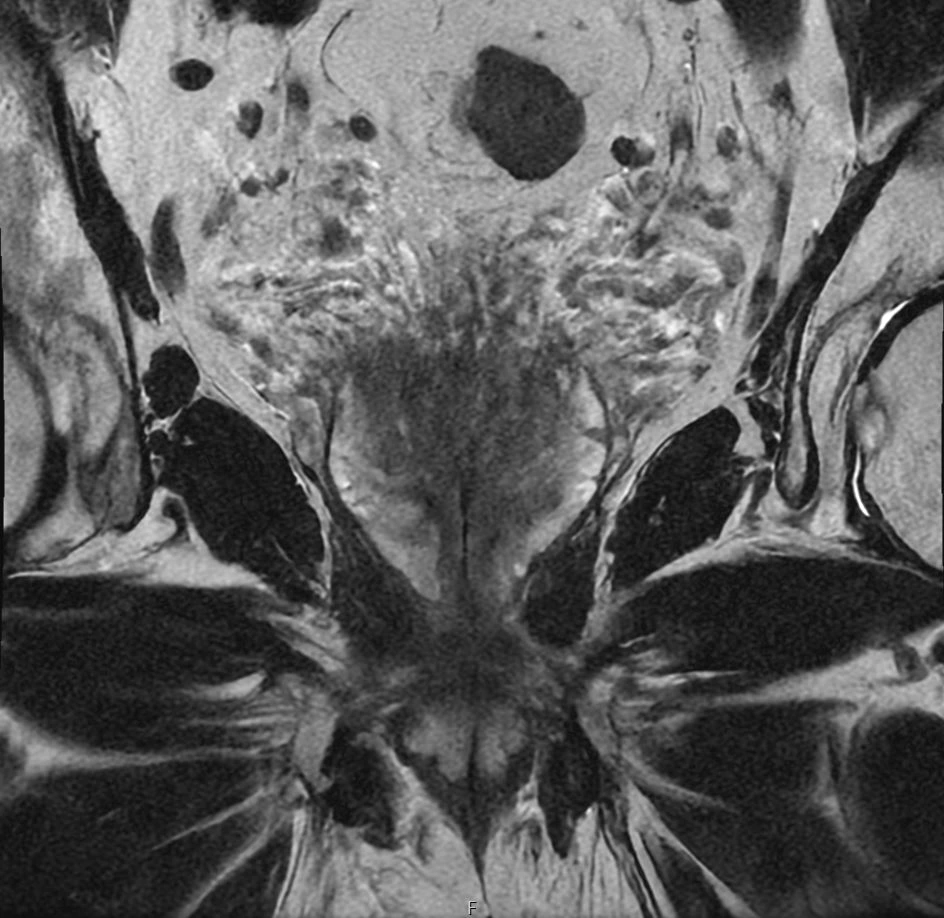

Eksempler på MR Scanninger

En MR-scanning af prostata er en skånsom undersøgelse, der giver meget detaljerede billeder af din prostatakirtel. Vores 3 tesla MR-scanner bruger et kraftigt magnetfelt og radiobølger til at skabe præcise billeder – helt uden brug af røntgenstråling.

Ved undersøgelsen får du en kontrastvæske, som sprøjtes ind i en blodåre. Kontrasten hjælper vores radiologer med at skelne mellem normalt prostatavæv og eventuelle sygdomsforandringer. Dette følger de gældende retningslinjer og giver langt mere pålidelige resultater end ældre undersøgelsesmetoder.

MR-scanningen kan vise forandringer i prostata, som hverken kan mærkes ved fysisk undersøgelse, ses på ultralyd eller opdages gennem en PSA-blodprøve. Denne høje præcision betyder, at undersøgelsen kan afklare, om der overhovedet er grund til at tage vævsprøver (biopsier).